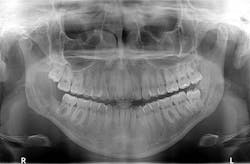

A healthy, 22-year-old female presents for a comprehensive examination. She has no chief complaints and no caries. The patient is referred to an oral surgeon for removal of wisdom teeth. Following that, all contact is lost (figure 1).